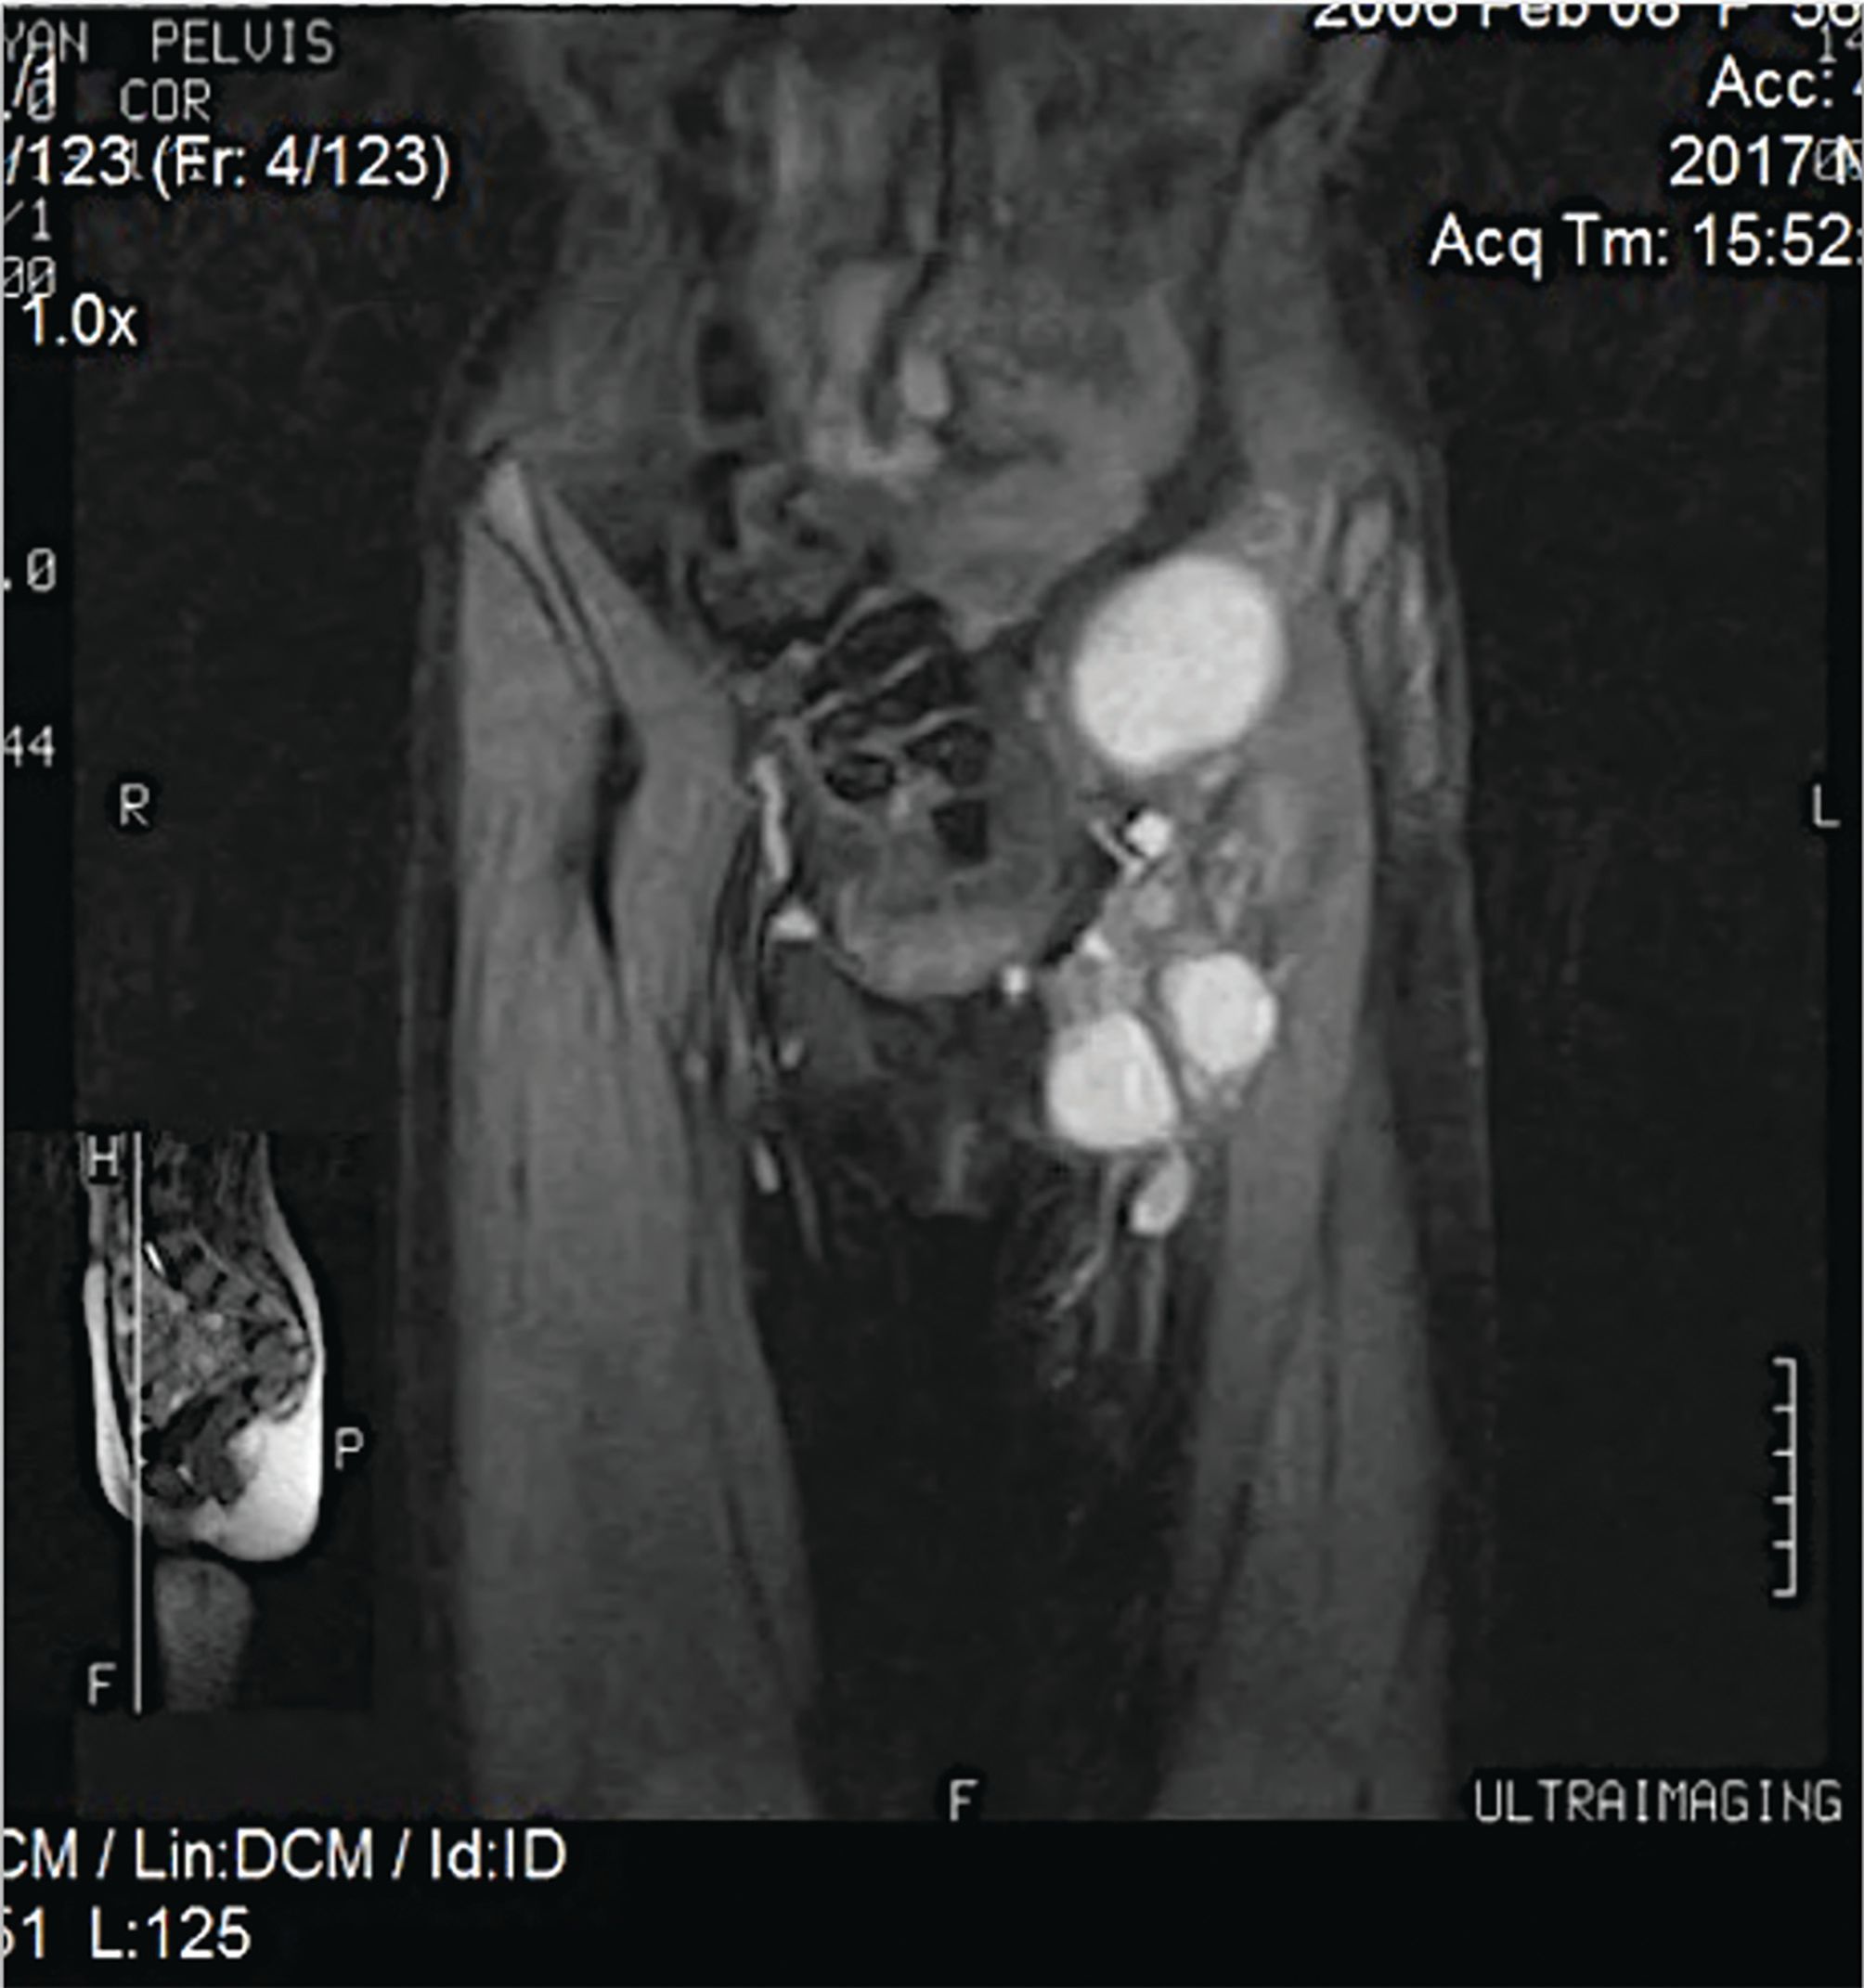

FIGURE 3a. The MRI Showed a Grape-Form Mass in the Abdominal Wall.

FIGURE 3b. The MRI Showed a Grape-Form Mass in the Abdominal Wall.

The patient’s parents initially refused further treatment. One year later, the patient noticed a painless mass beneath the postoperative scar on the anterior abdominal wall (Figure 2). The MRI revealed a grape-shaped, well-defined soft tissue mass in the left lower quadrant of the abdominal wall, measuring 15 cm (Figure 3). The CT showed left inguinal lymphadenopathy without signs of distant metastases. A bone scan revealed no abnormalities. A tumor biopsy confirmed disease relapse.